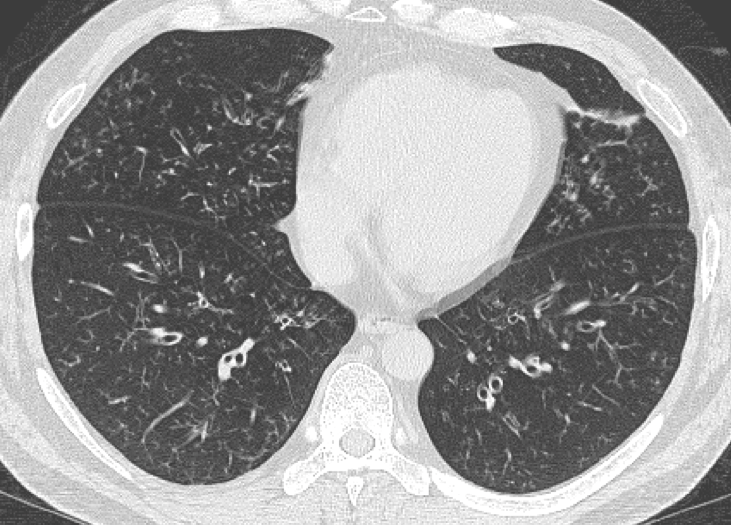

小児科医は、お子様の肺の音に耳を傾け、呼吸時の喘鳴やパチパチ音などの特定の騒音を確認します。 NHS によると、喘息や嚢胞性線維症など、他の病状の兆候がない限り、さらなる検査は必要ありません。

- 胸部X線検査、肺炎の兆候を発見する

肺炎は、肺胞が液体または膿で満たされる肺の感染症です。細気管支炎は、肺の細い気道である細気管支の炎症です。どちらの症状も肺に咳、粘液、その他の呼吸器症状を引き起こします。